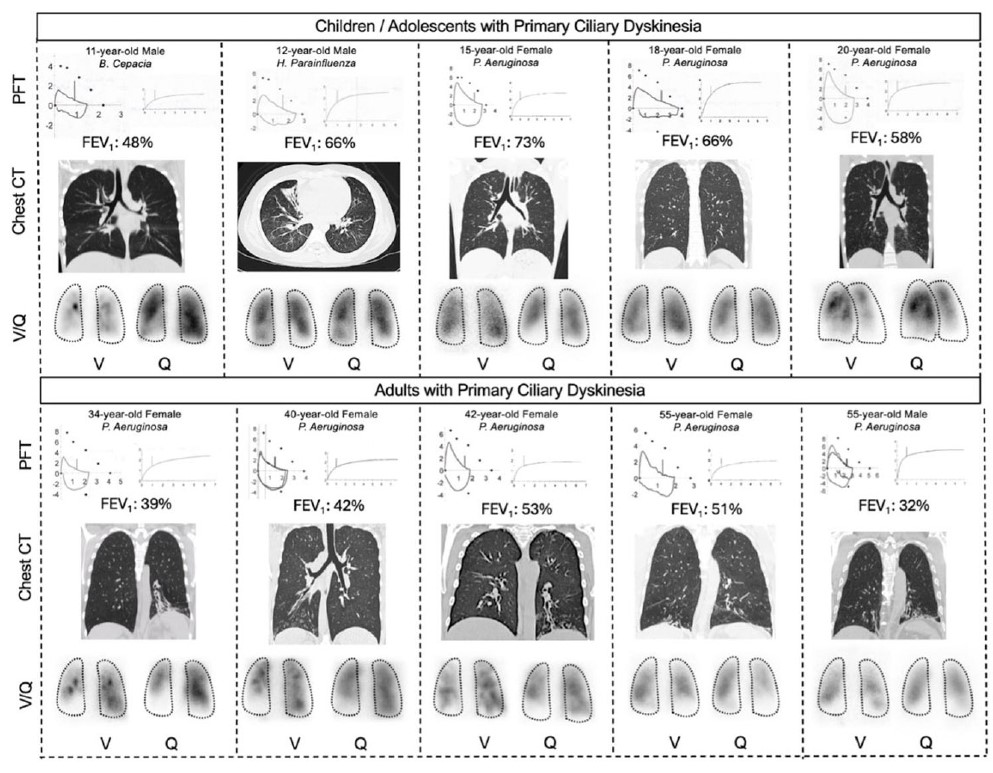

[Electronic Publication Date: March 25, 2026]Tanisha Dighe, Shyam Subramanian, Sneha Reddy, Munish Sharma and Salim Surani